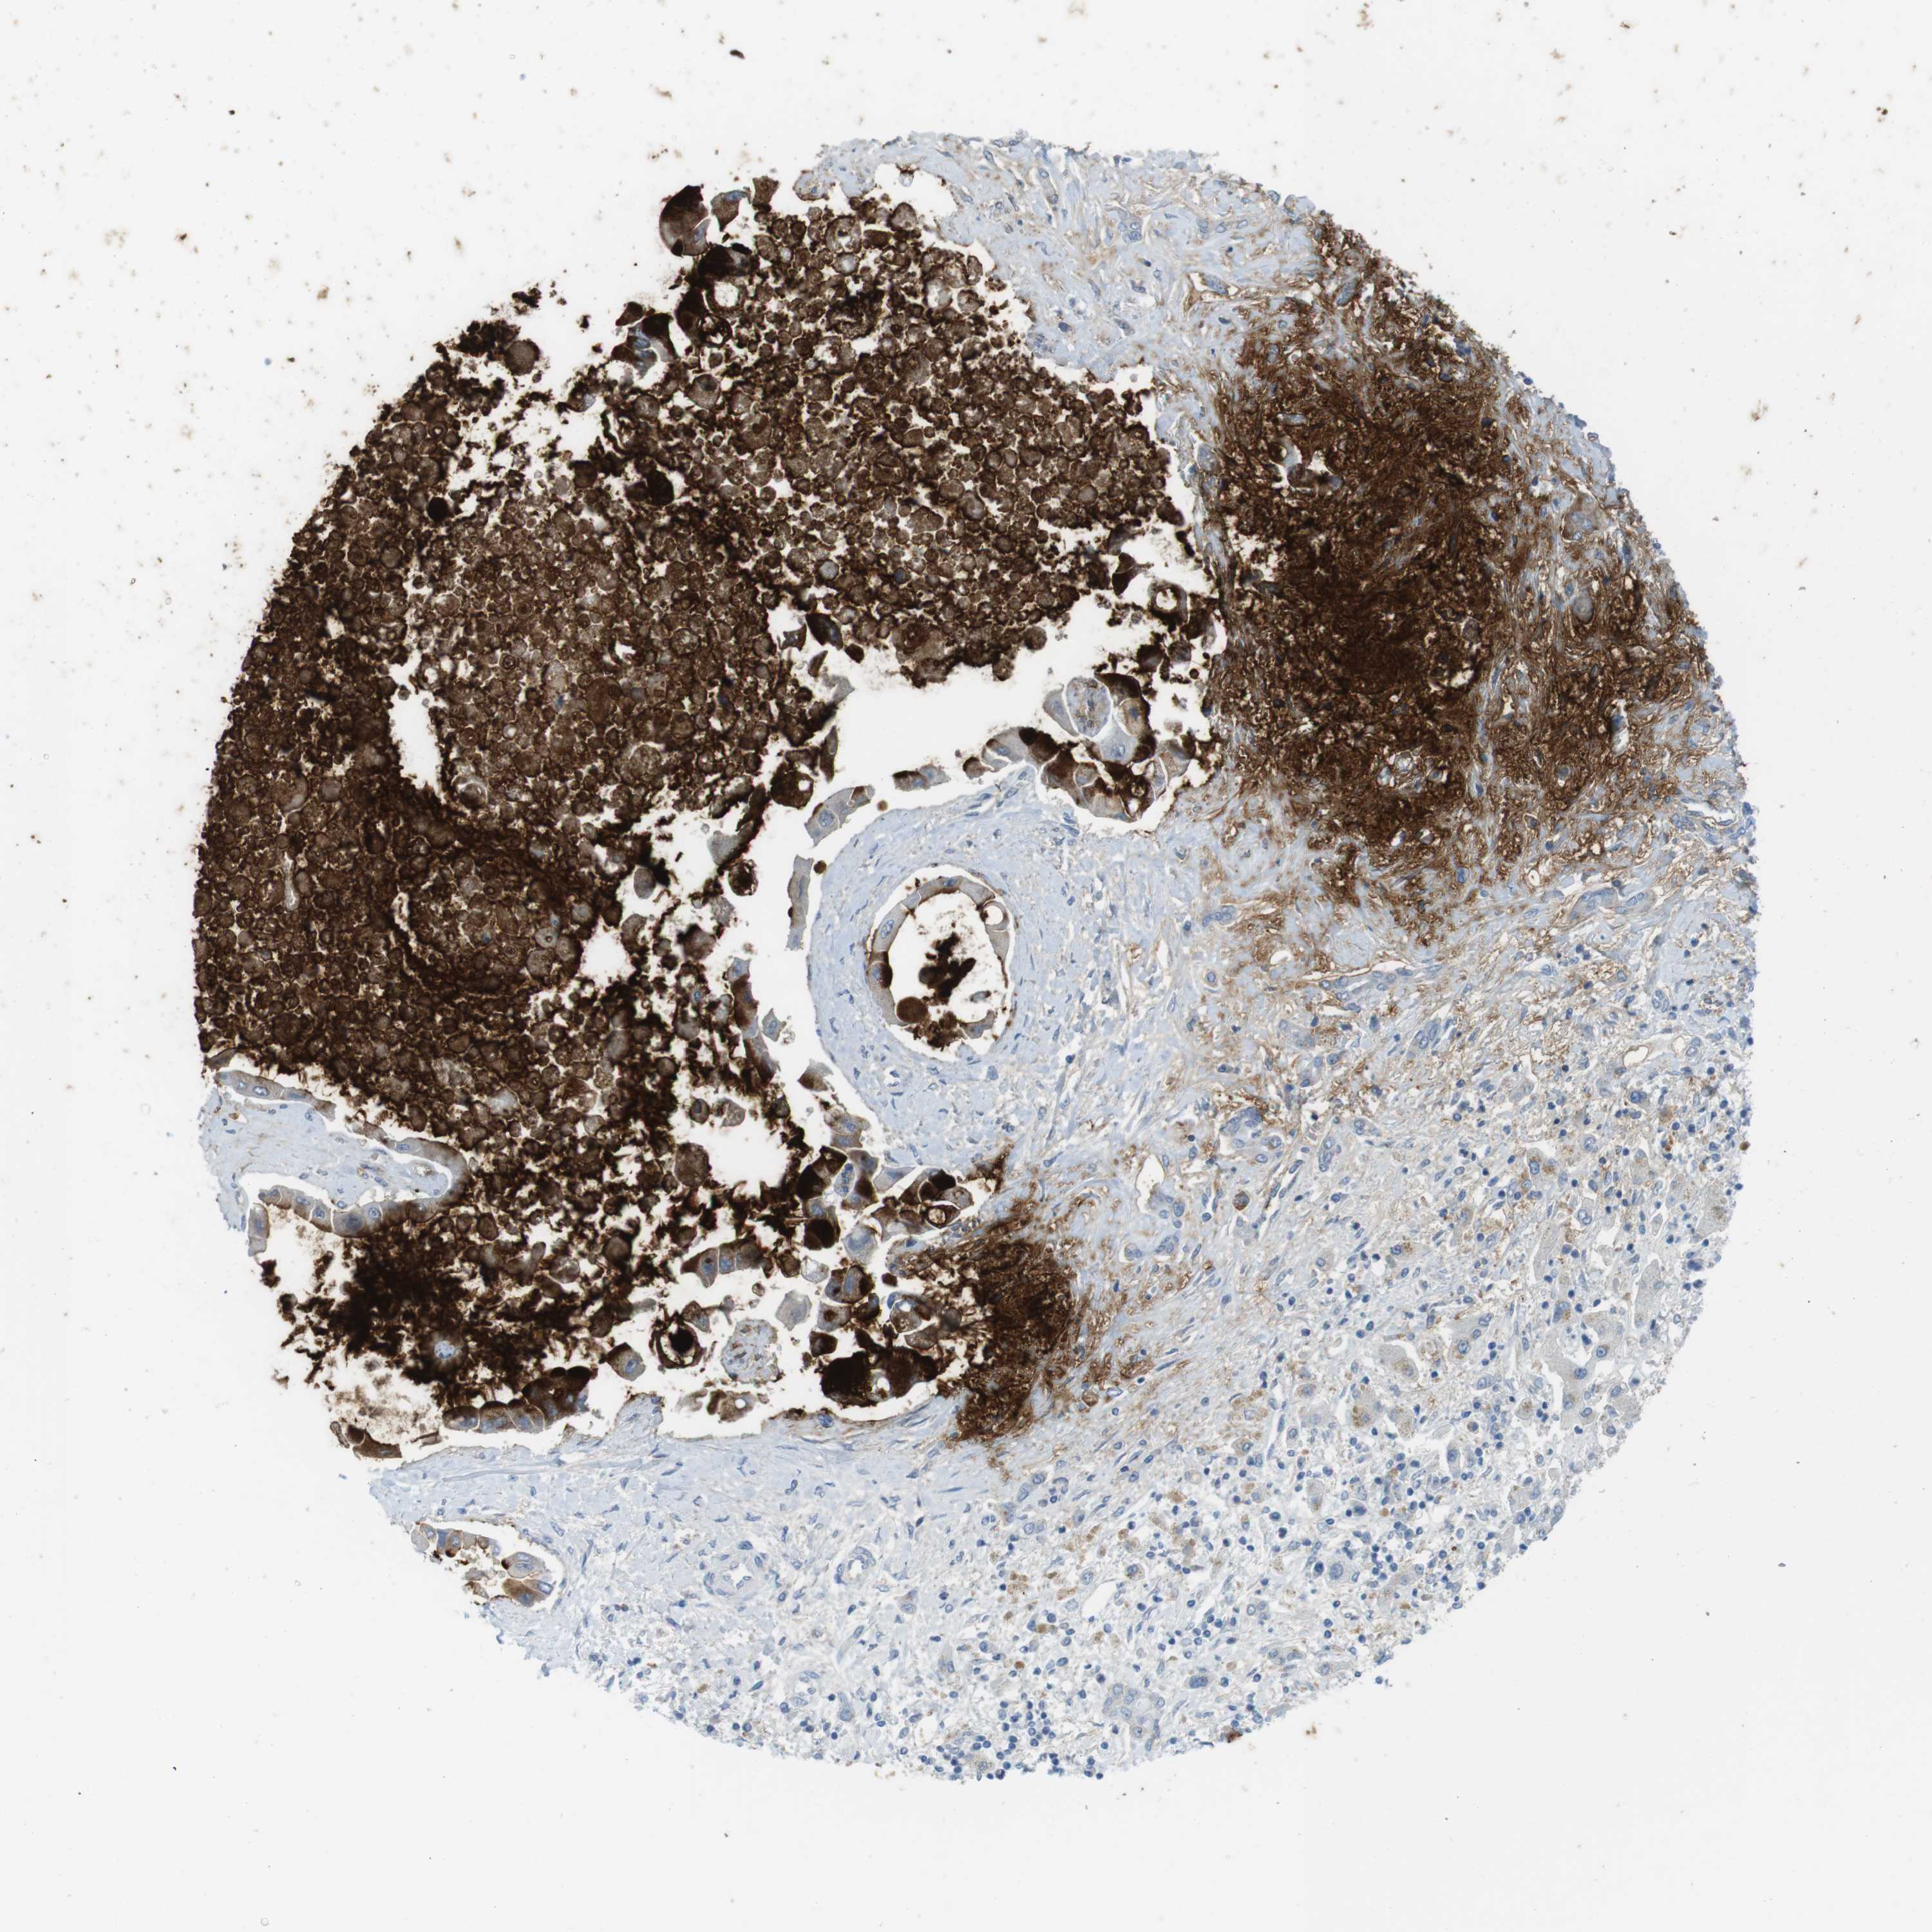

LIVER CANCER - Protein expressioni

A mouse-over function shows sample information and annotation data. Click on an image to view it in a full screen mode. Samples can be filtered based on level of antibody staining by selecting one or several of the following categories: high, medium, low and not detected. The assay and annotation is described here.

Note that samples used for immunohistochemistry by the Human Protein Atlas do not correspond to samples in the TCGA dataset.

Antibody stainingi

Antibody staining in the annotated cell types in the current human tissue is reported as not detected, low, medium, or high, based on conventional immunohistochemistry profiling in selected tissues. This score is based on the combination of the staining intensity and fraction of stained cells.

Each image is clickable and will lead to virtual microscopy that enables deeper exploration of all samples and also displays staining intensity scores, fraction scores and subcellular localization as well as patient and tissue information for each sample.

Antibody HPA008246

Antibody CAB009396

Staining

High

Medium

Low

Not detected

Intensity

Strong

Moderate

Weak

Negative

Quantity

>75%

75%-25%

<25%

None

Location

Nuclear

Cytoplasmic/membranous

Cytoplasmic/membranous,nuclear

Cholangiocarcinoma

Carcinoma, Hepatocellular, NOS